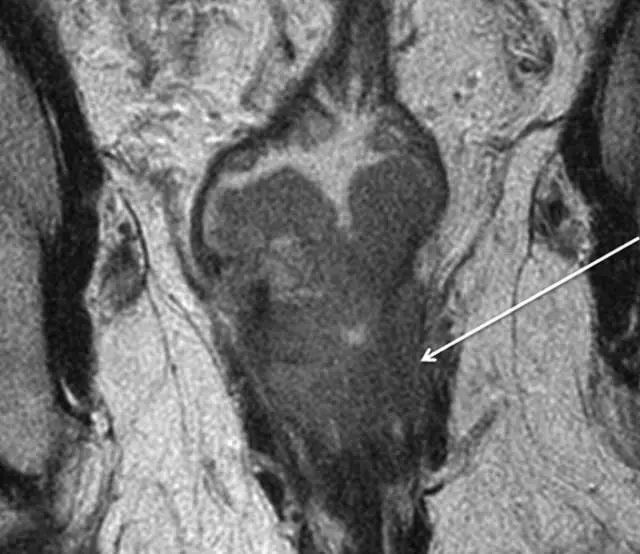

58 岁低位直肠癌男性, T2 加权冠状 MR 图像显示左侧入侵到内侧平面(箭头)。